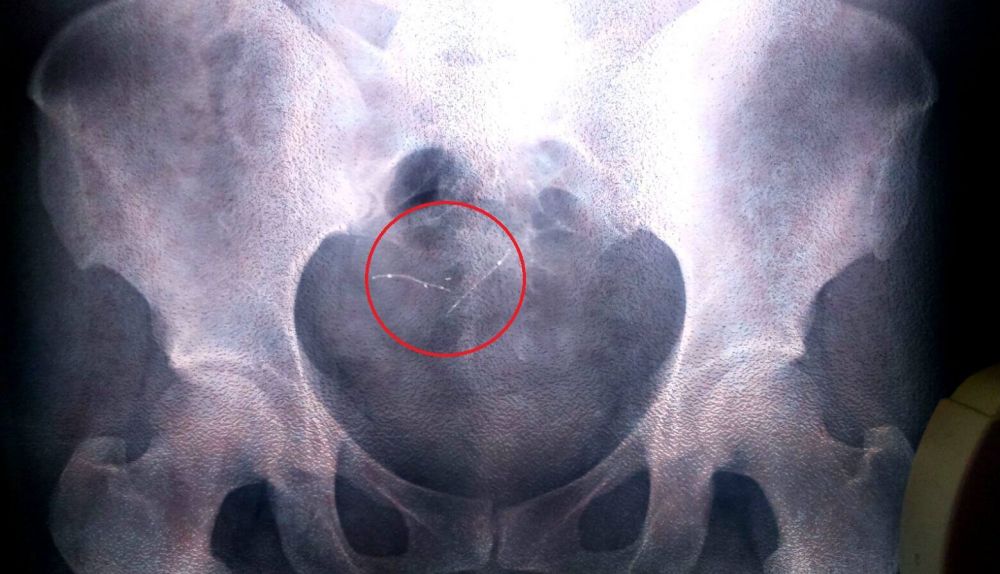

“El 18 de abril del 2012”, dice de la fecha en la que los dos muelles comenzaron a formar parte de su cuerpo, casi machacando cada una de las palabras. Lo que a priori debería haberle aportado la tranquilidad de evitar un futuro embarazo, le ha truncado su día a día. En la primera revisión de los seis meses informó a los facultativos de los fuertes dolores que padecía en el abdomen. Tras las pruebas pertinentes, y mediante histeroscopia, comprobaron que uno de los muelles estaba desplazado, “casi afuera”. La única explicación que recibió fue que algunos se rechazan. Punto. “Me lo quitaron a dolor. El mismo doctor que me dio la charla, me lo colocó y me lo quitó”. Después ha intentado hablar con él, realizarle consultas y le ha resultado imposible. El personal que le atiende solo le da esquinazo cuando intenta contactar con él. Un par de meses después, inevitablemente, fue intervenida para practicarle la ligadura de trompa. Al continuar con las molestias la extracción del otro dispositivo, pero fue tarde. La intervención ya estaba programado solo para la ligadura de una de las trompas. Y así fue.